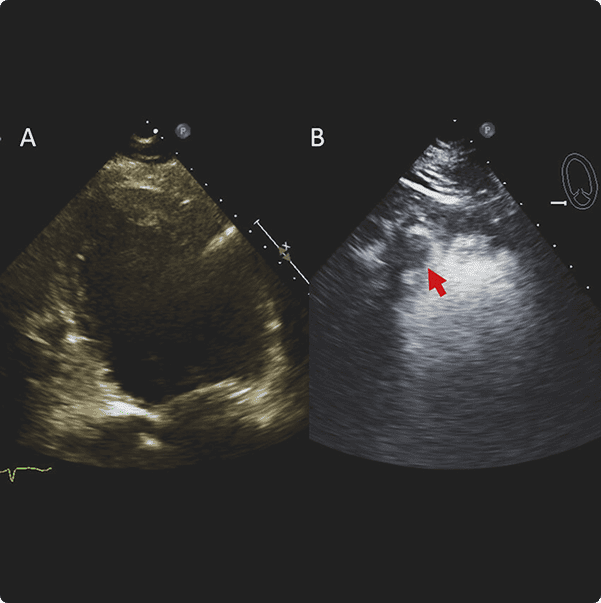

Contrast Transthoracic Echocardiogram (cTTE): Enhancing Heart Imaging Precision

A Contrast Transthoracic Echocardiogram (cTTE) is an advanced cardiac imaging test that employs ultrasound and a contrast agent to obtain clearer and more detailed images of the heart. This diagnostic procedure enhances our ability to visualize and assess specific cardiac structures, providing valuable information for a comprehensive evaluation of your heart health.

During a cTTE, a contrast agent is introduced into the bloodstream through a vein, typically in the arm. This contrast material enhances the visibility of the heart chambers, allowing for a more precise and detailed examination.

Improved Visualization: cTTE is particularly useful for obtaining clearer images in patients where standard echocardiography

may provide limited information.

Diagnostic Accuracy: It aids in the accurate diagnosis and assessment of various heart conditions, including structural abnormalities and heart valve disorders.